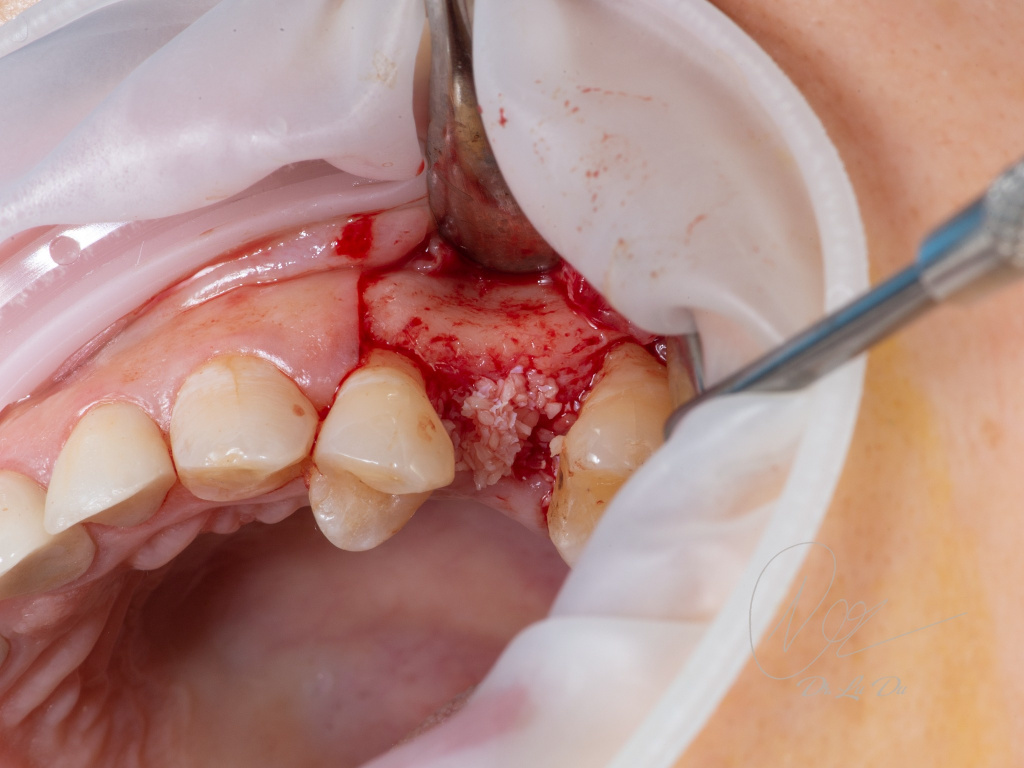

Имплантация AnyRidge с двусторонним закрытым синус-лифтингом.

Осложнения: правосторонний гайморит.

Кейс MINEC: Dr Lu Du